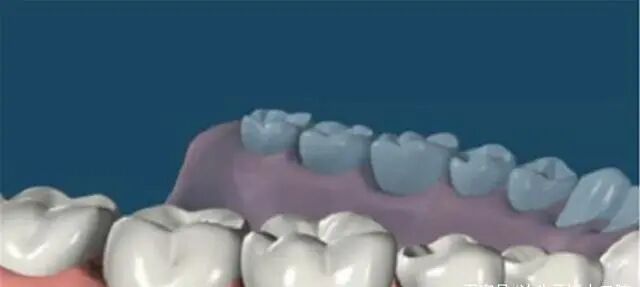

2、安装愈合基台

然后使种植体穿出牙龈,接下来就等待软组织成形就可以了。